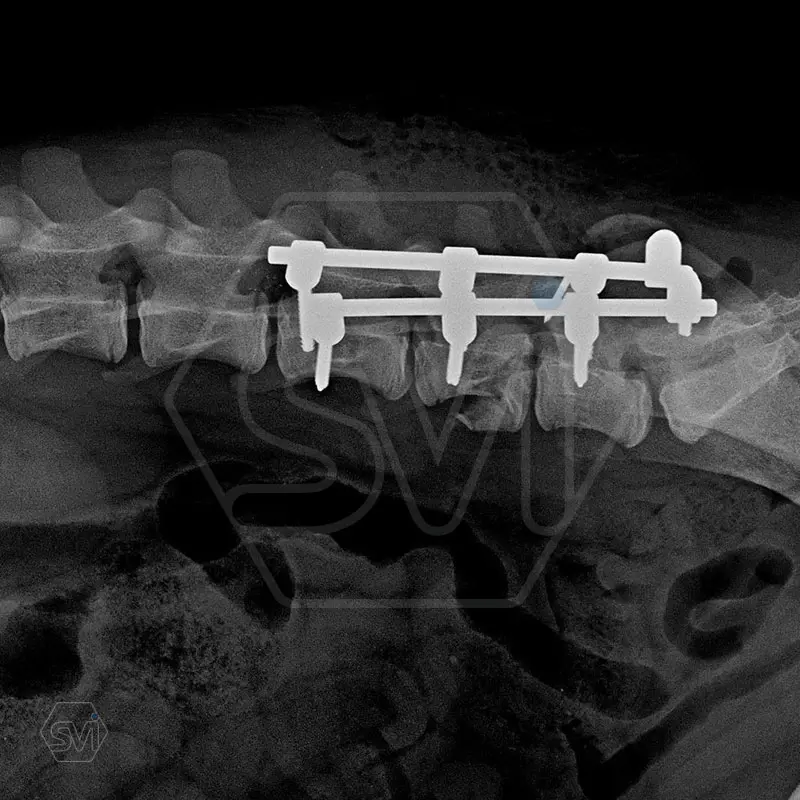

L6 vertebral body fracture fixation with 2.7-mm SOP-LC system

We performed a laminectomy of L7 and then performed fixation with a 4-4 clamp, bilateral 2.7-mm SOP-LC system. Control x-rays were taken at 6 and 12 weeks after surgery. Based on the video, in our opinion, the dog has recovered… :)